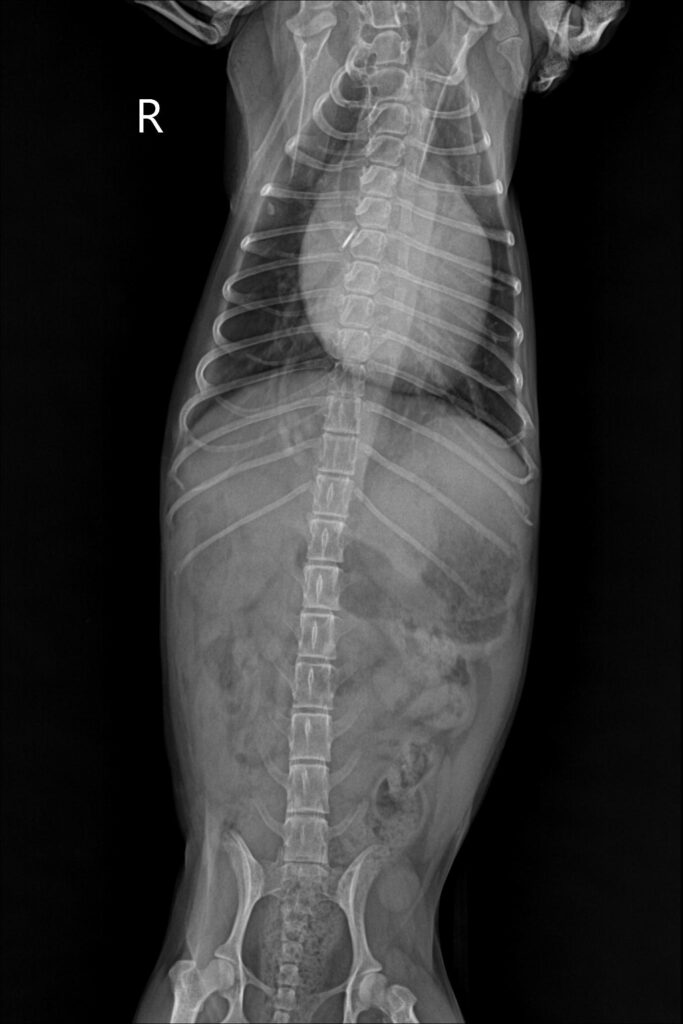

입원 5일차 방사선 검사 / 출처: 미래동물의료센터

입원 5일 차에 재촬영한 흉부 X-ray에서 우측 후엽에 보이던 폐침윤 소견이 눈에 띄게 감소한 것을 확인할 수 있었습니다. 또한 산소방 외 환경에서도 호흡수가 안정적으로 유지되고 노력성 호흡이 관찰되지 않는 점을 확인한 후 퇴원을 결정하였습니다.

현재는 심장 질환과 폐수종 재발 가능성을 고려하여 약물 조절과 함께 지속적인 경과 관찰을 진행하고 있습니다. 이 환자처럼기존 심장 질환을 관리 중인 노령견의 경우, 호흡 변화가 단순한 컨디션 저하가 아니라 폐수종의 신호로 나타날 수 있습니다. 특히 “하루 사이 숨 쉬는 모습이 달라졌다” “가만히 있어도 숨이 가빠 보인다”는 변화는 빠른 평가와 개입이 필요한 중요한 단서가 됩니다.